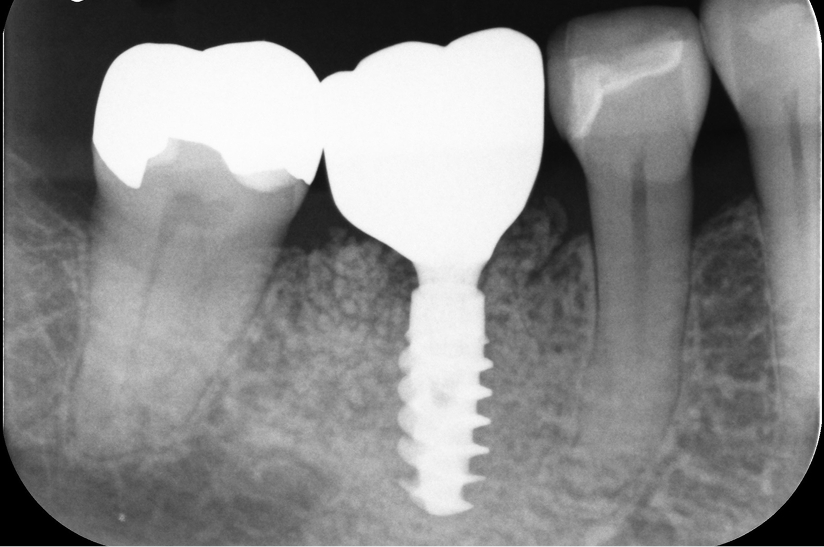

右下奥歯で噛むと痛みがある

診断

歯周病による歯槽骨吸収および垂直性歯根破折

治療方針

遊離端欠損となるため、入れ歯またはインプラントが選択肢となる症例。 硬いものをしっかり噛みたいという希望があり、インプラントを選択した。

また、水平的な骨吸収が認められたため、 インプラント埋入と同時にGBRを併用する方針とした。

治療内容

抜歯即時インプラント埋入およびGBR

治療期間

約6〜8ヶ月(骨造成を伴うため)

治療費用

1,500,000

結果

水平的に十分な骨幅が獲得され、インプラントの安定も良好に得られている。

治療の

リスク

創部の早期裂開が生じた場合、移植材の除去および再手術が必要となる可能性、下顎神経麻痺、出血・血腫

考察

骨量が不足する症例においては、GBRを先行して行う方法も選択肢となる。

本症例では抜歯窩からの血液供給も利用し、インプラント埋入と同時にGBRを行うことで、良好な骨造成と治癒が得られた。

その結果、治療期間の短縮と外科的侵襲の低減が可能となった。